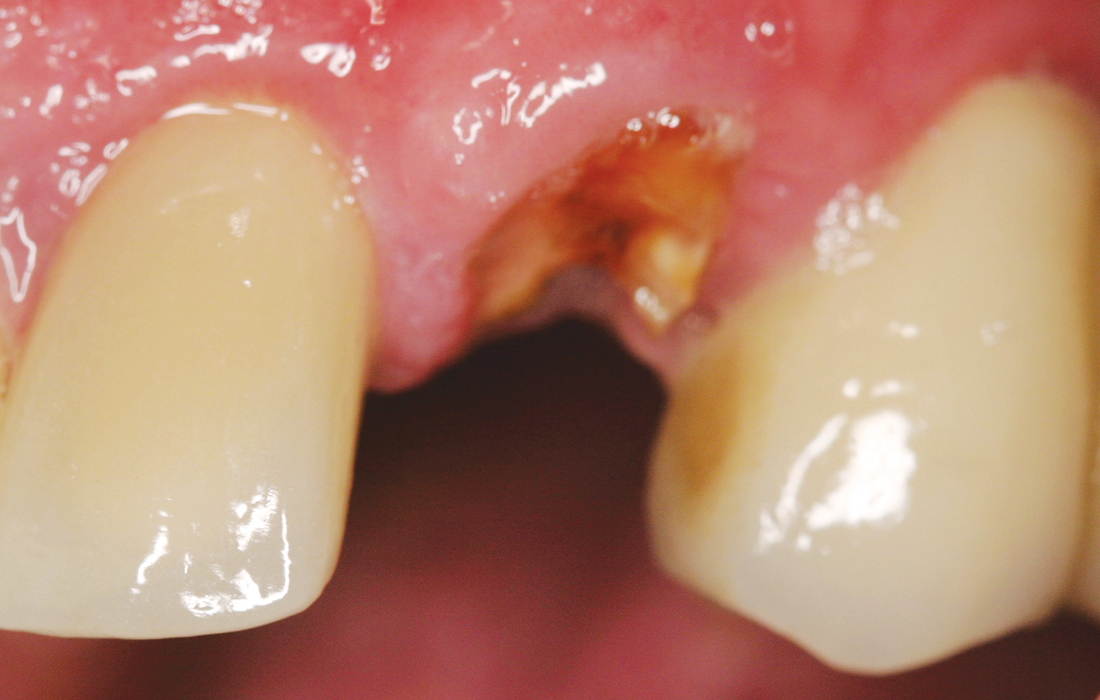

Hahn Clinical Case Image 4 CSM V15I2

Hahn Clinical Case Image 5 CSM V15I2

Hahn Clinical Case Image 6 CSM V15I2

The patient presented with a horizontally fractured tooth #11 and was in a great deal of distress due to the esthetic issues this created. After extracting the tooth, a Hahn Tapered Implant was placed. The pronounced thread design eased placement 1 mm from the facial aspect of the extraction site. High primary stability of 45 Ncm was achieved, allowing for the placement of an immediate provisional crown.